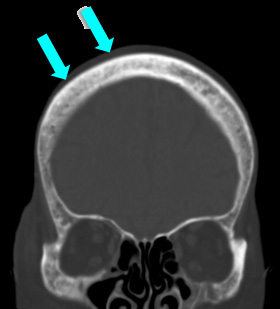

CTの骨条件では、頭蓋骨に不均一な骨硬化像を認める。

頭部単純CT